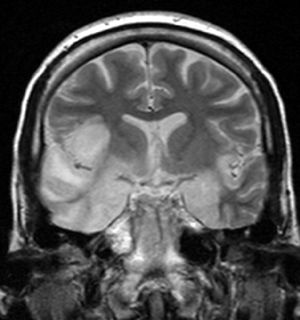

coronal T2-weighted MR image shows high signal in the temporal lobes including hippocampal formations and parahippogampal gyrae, insulae, and right inferior frontal gyrus. A brain biopsy was performed and the histology was consistent with encephalitis. PCR was repeated on the biopsy specimen and was positive for HSV | |